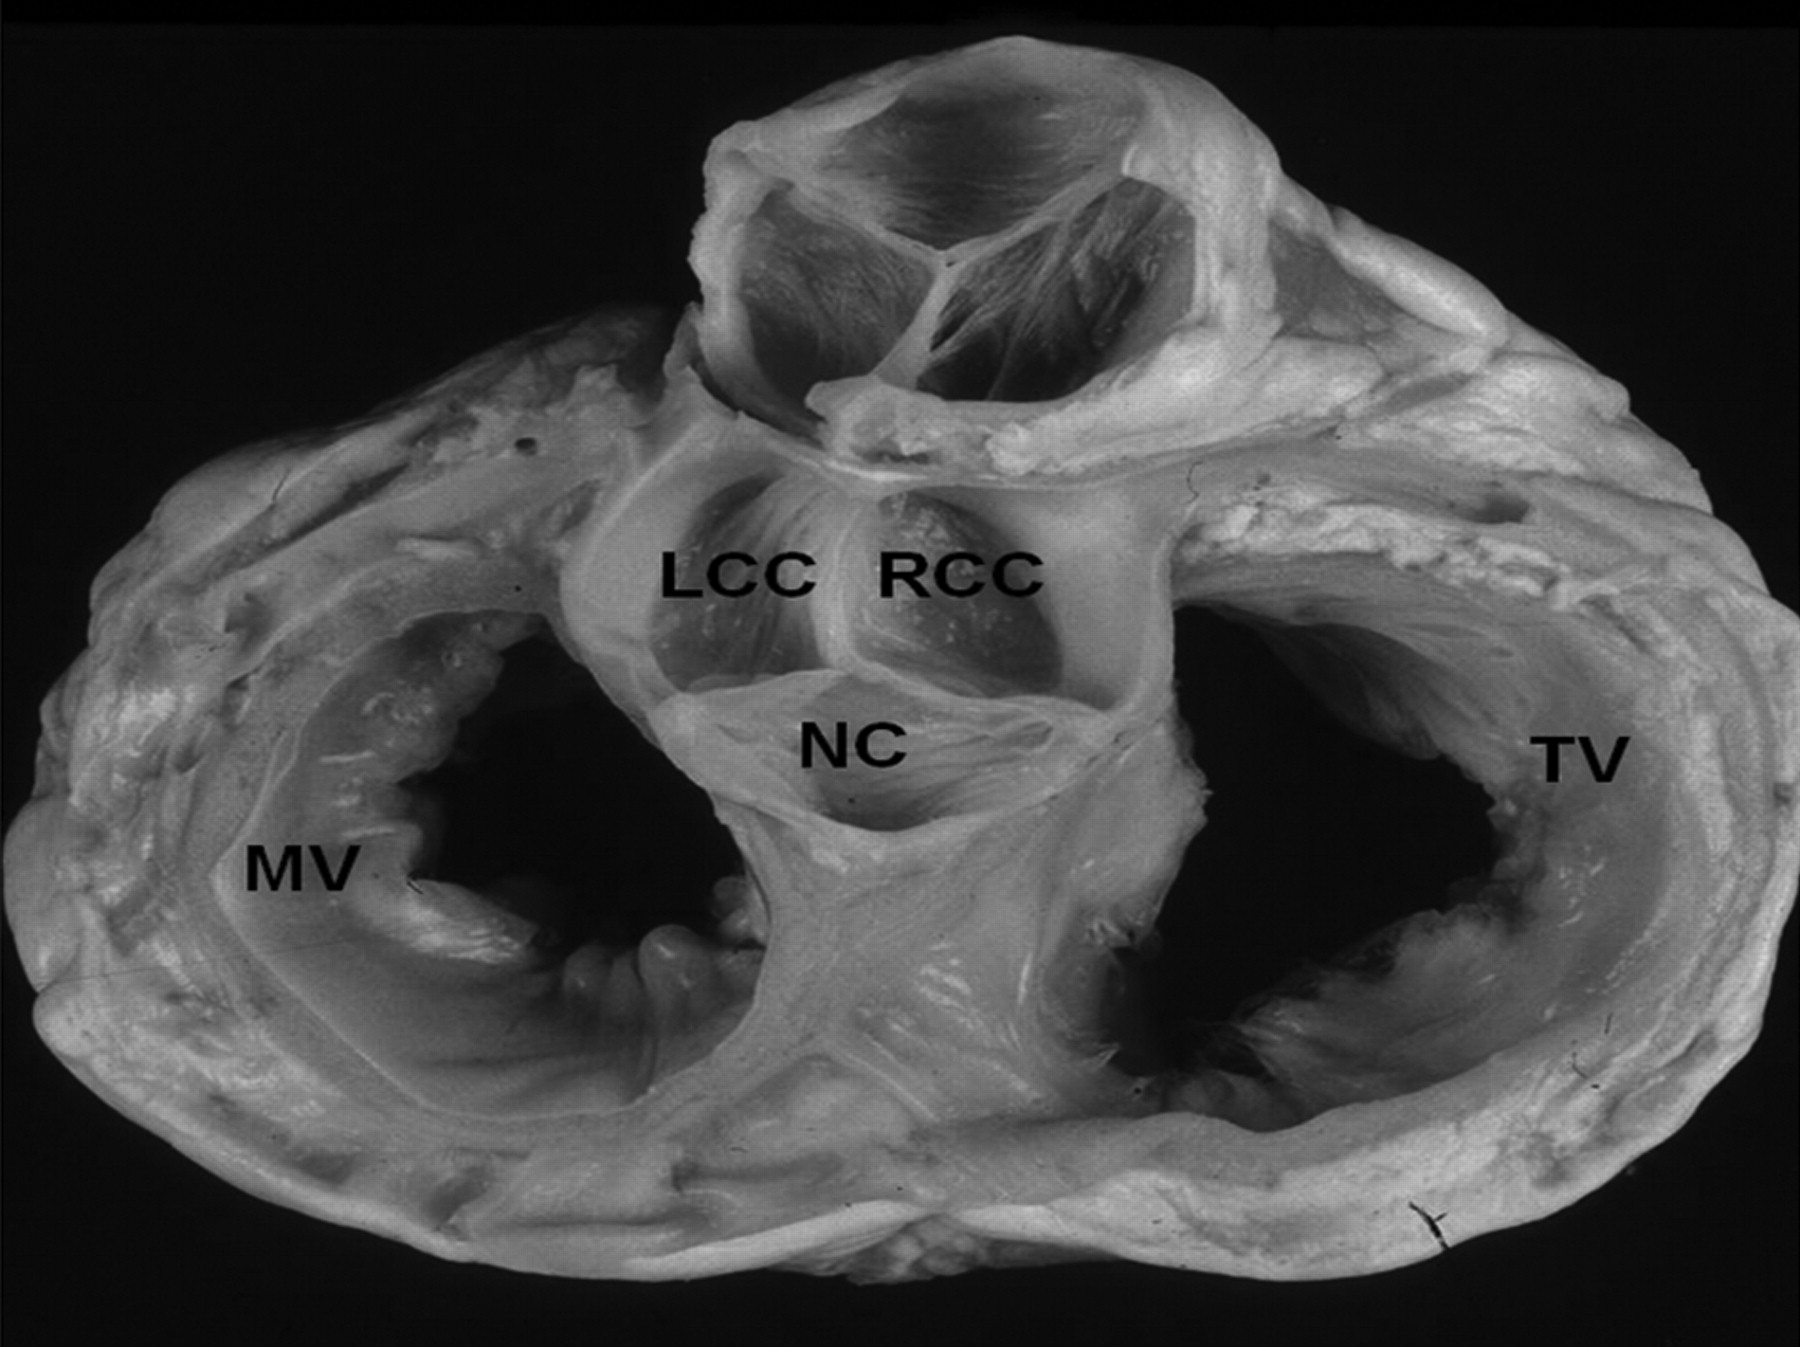

Anatomy

Outflow tracts relation

heart_base.jpg

Niloufar Tabatabaei and Samuel J. Asirvatham. Circulation: Arrhythmia and Electrophysiology. 2009;2:316–326

LVOT

aortic_sinuses.jpg